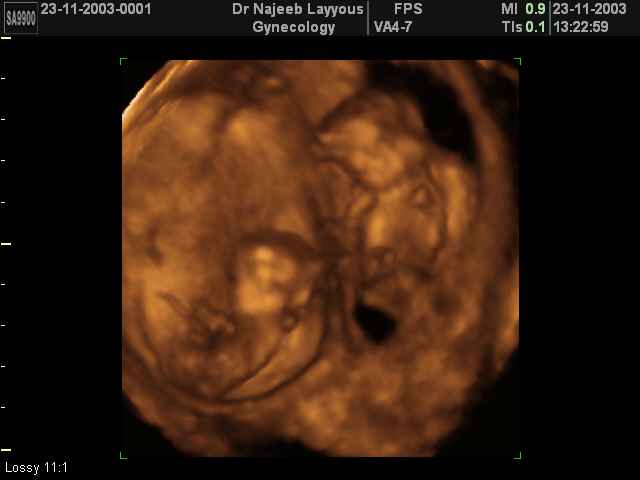

- 3D Photos échographie de grossesse multiple